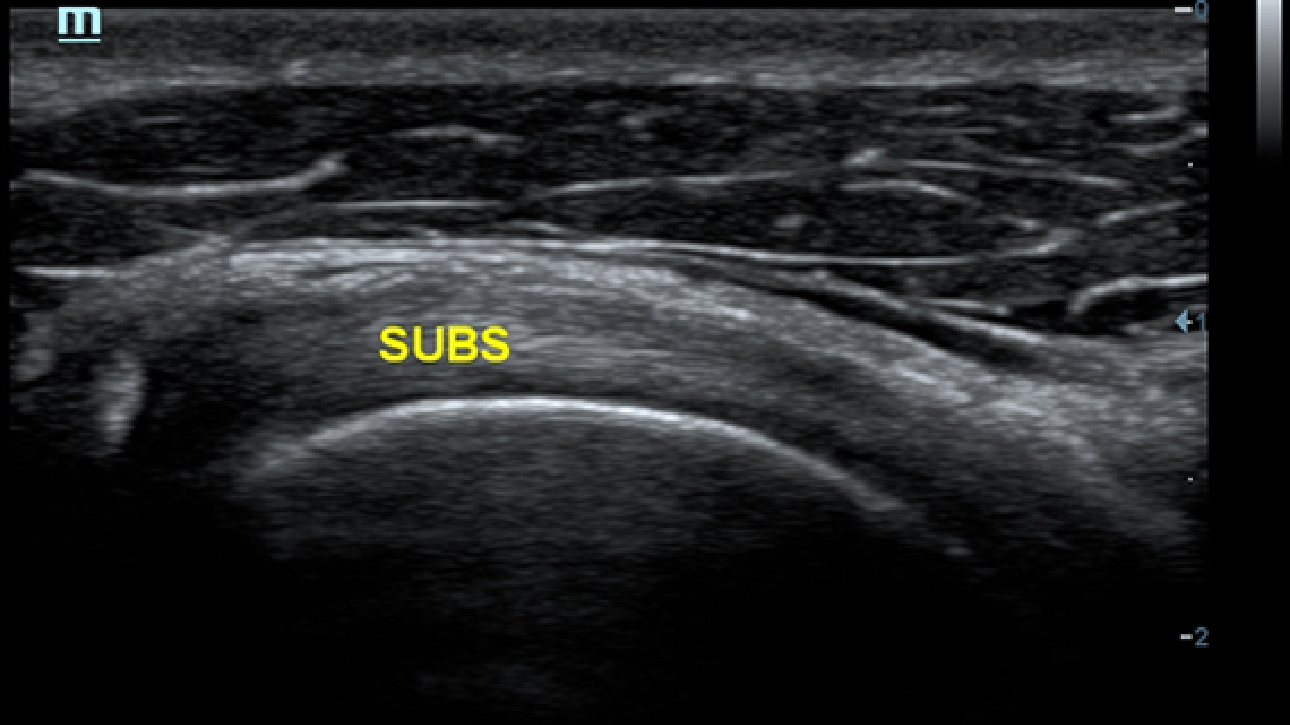

X-Insight ??? ??? ??? ??? ?? ??? ?? ?? ??????.

?????? ??? ???? ?? ???? ??? ??? ??? ???? ??? ??? ??? ?? ??? ???? ?????. ??? ?? ????? ???? ???? ??? ?? ??? ???? ?? ???? ??? ???? ???? ????.

???? ?? ??? ?????, X-Insight???? ??? DC-60 Exp ?? ??? ???? ???? ?? ??? ?? ??? ?? ???? ?????.

X-Insight??? ??? DC-60 Exp? ??? ??? ?? ?? ???? ???? ???(eXpress) ???, ???(eExceptional) ?????, ???? (eXceeding) ?? ??? ?? ????, ??? ???? ??? ??? ?? ???? ?????.